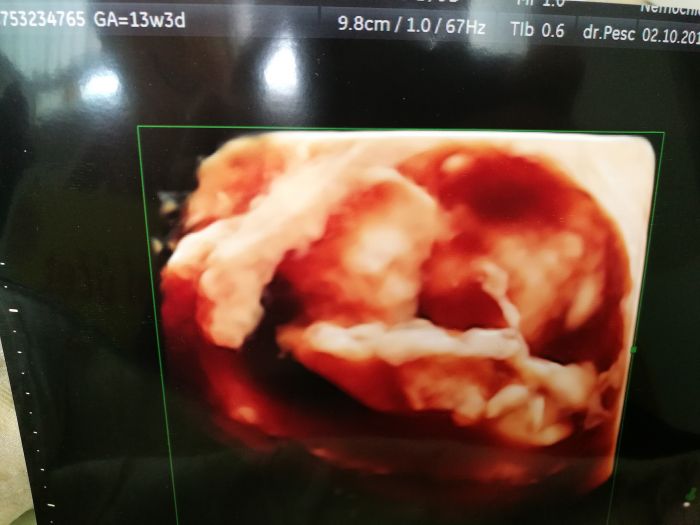

Autor: Erika87 27.11.2018 v 05:27

Holky dekuju, mne 3d delali uz na prvnim screeningu, chodim na nej do nemocnice, tam mi daji obrazek automaticky, jeste pujdeme v tom 30tt. Tohle je z toho prvniho screeningu